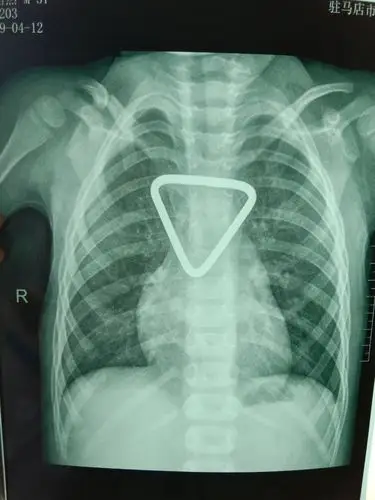

骨伤科锁骨骨折患儿经中医手法整复后愈合良好